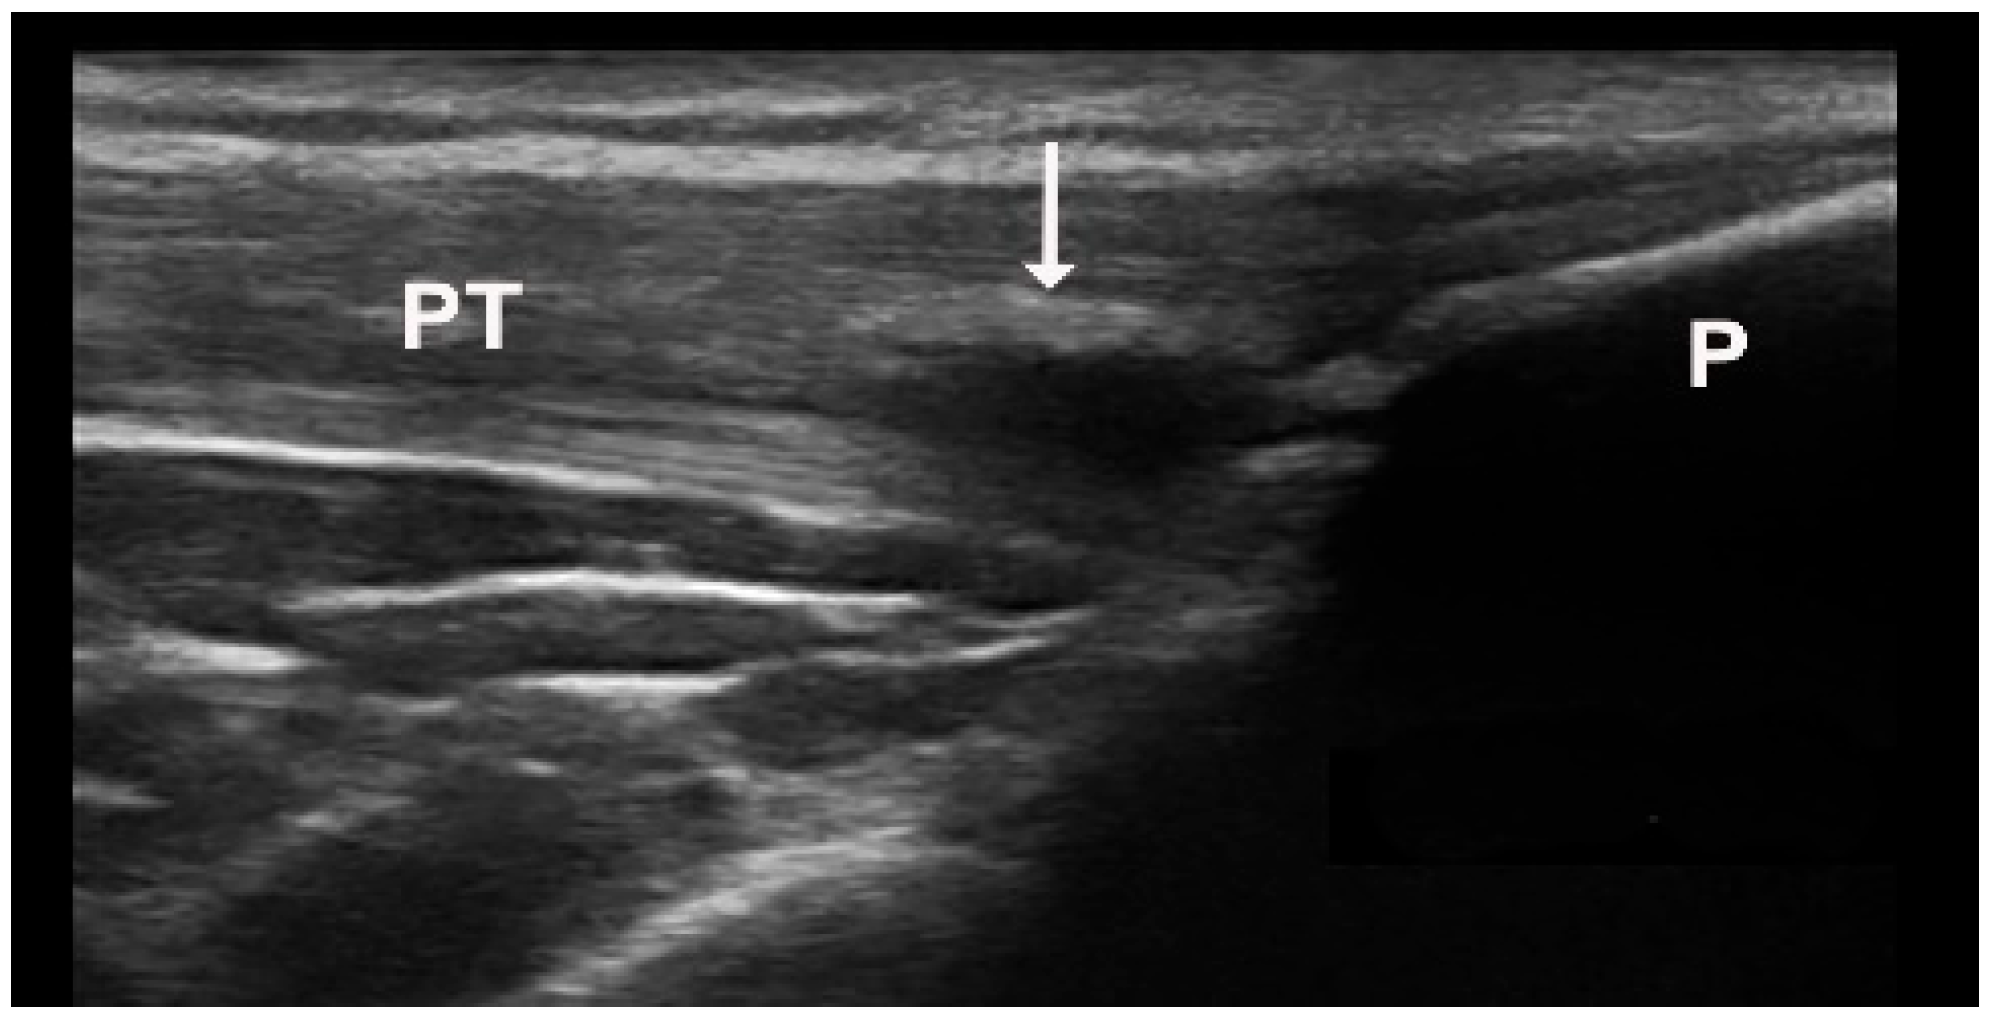

Figure 3.

Intratendinous soft tophus visible in longitudinal view of the proximal insertion of the patellar tendon ((A)—grayscale, (B)—Power Doppler mode). P—patella, PT—patellar tendon, arrow—intratendinous soft tophus.

Figure 4.

Intratendinous hard tophus visible in longitudinal view of the distal insertion of the patellar tendon. Notice the posterior shadowing from the tophus. P—patella, PT—patellar tendon, arrow—intratendinous hard tophus.